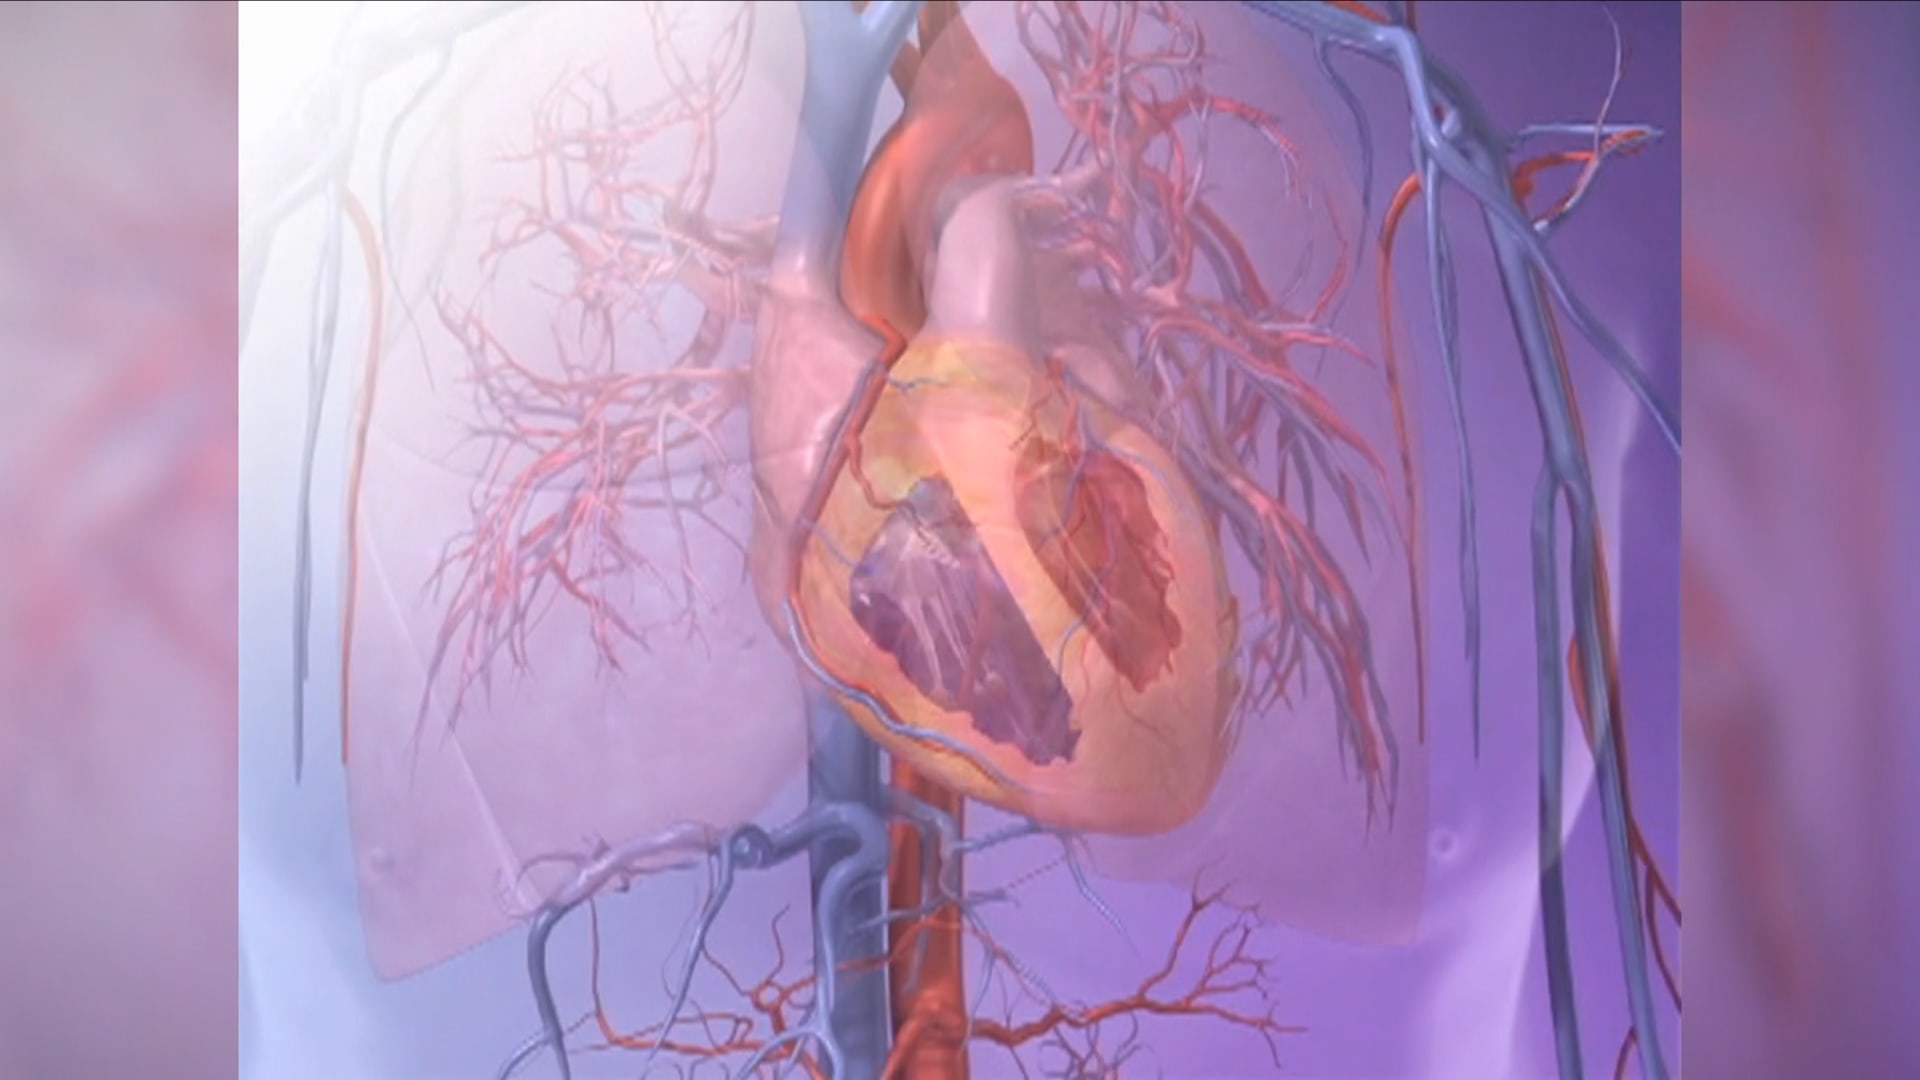

تكلفة الفقر الباهظة.. الضغوط المالية تؤثر على صحة قلبك وشبابه

أظهرت دراسة جديدة نُشرت في مجلة “Mayo Clinic Proceedings” أنّ القلق بشأن المال والأمن الغذائي قد يُسرّع من شيخوخة القلب أكثر من عوامل الخطر التقليدية لأمراض القلب والأوعية الدموية.